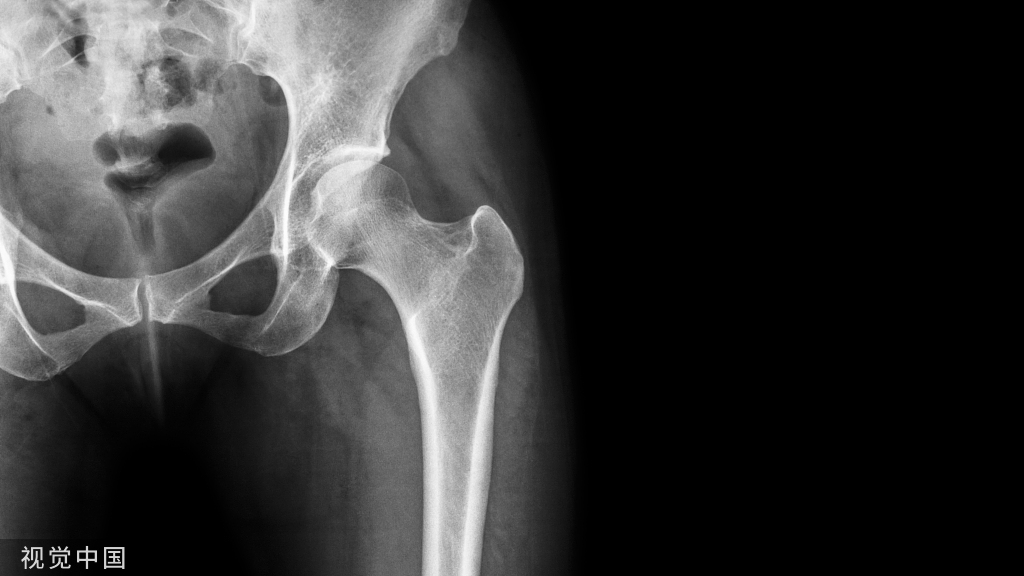

土耳其伊斯坦布尔xxx Baltalimani骨病医院的学者发现了一个脊柱严重角状后凸(≥90°)正位X线片的影像学征象,将其命名为 Baltalimani征

土耳其伊斯坦布尔xxx Baltalimani骨病医院的学者发现了一个脊柱严重角状后凸(≥90°)正位X线片的影像学征象,将其命名为 Baltalimani征。

Baltalimani征阳性:脊柱严重角状后凸(SAK)的顶椎相邻椎体处于垂直翻转状态。在正位x线片上可以观察到椎体轮廓呈轴位观。

Baltalimani征阳性的正侧位X片示例。这种严重成角压迫使得脊髓损伤发生几率比阴性征象增加了61.9%